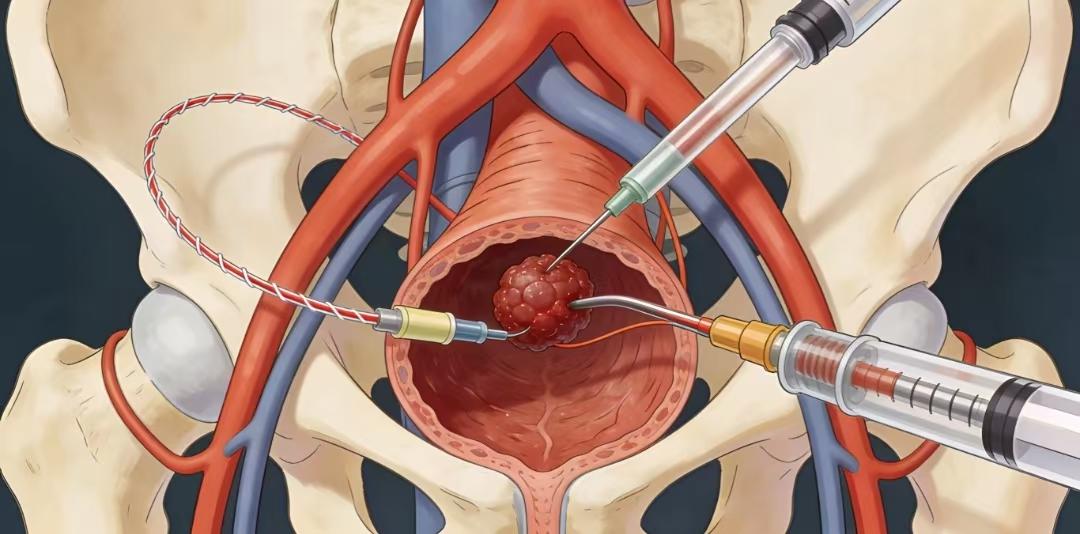

来看看心脏血管斑块破裂是什么样子的。一个 75 岁的男性患者,在医院就诊时,突发心脏骤停倒地,经胸外按压积极抢救后恢复意识。 紧急做了冠状动脉造影,发现是前降支中段一个不稳定斑块出现的破裂,局部有血栓形成。这就是导致患者突发意识丧失的原因。导丝通过前降支病变后,植入支架三枚,把斑块附近的有动脉硬化的血管全部覆盖,血流恢复通畅。 其实这里的狭窄本身并不严重,狭窄程度大约在 70% 左右。突然出现急性心肌梗塞,并不是说堵塞非常严重,而是一些不稳定的斑块突然破裂,导致的局部血栓形成,进而堵塞整个血管。 冠心病的治疗,一方面是预防血栓,另外一方面是尽量稳定动脉硬化斑块,让其不容易破裂。稳定斑块的方法,最主要的是降低低密度脂蛋白胆固醇,一旦发现有冠心病,最好把低密度脂蛋白胆固醇降低到 1.8 以下,最好降低到 1.4 以下。这样斑块才会更加稳定,不容易破裂,也就不容易突发急性心肌梗塞了。